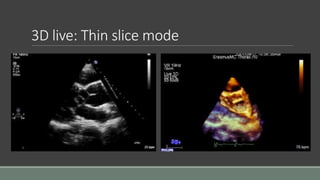

3D live: Thin slice mode

3D live: Thinslice mode

• #29 Practically, there are limitations on how much data a probe can collect at once, and of course limitations on how to display 3D data on the 2D screen. With a 3D probe, there are different modes to chose from, each being optimized for different applications. Acquisition of the image remains a frame by frame job, so first of all, imaging the whole 3D sector is not feasible all at once, because the speed of acquisition of each frame can never be quick enough compared to the motion of cardiac structures. At best the probe can image live a limited volume, a thin slice. If better resolution is required, then a zoom mode is usually available to focus the imaging resource on a selected volume, that may be thicker. The full volume is not exactly imaged live.

• #30 Thin slice mode is rather straight forward. It is somehow just a 2D mode view a bit of view on adjacent plans.